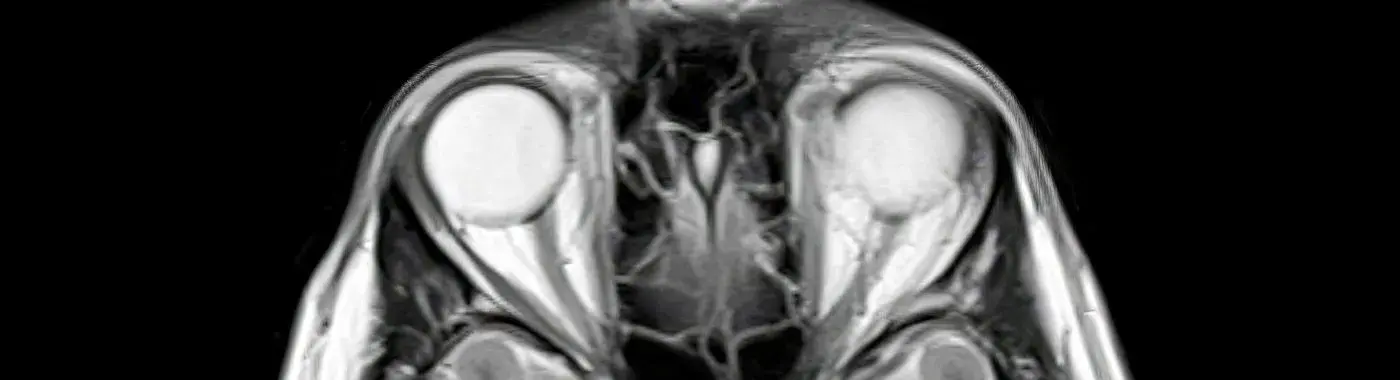

Optic disc drusen (ODD) is a condition characterized by the accumulation of small, calcified deposits in the optic nerve head, which can lead to various visual disturbances. While often asymptomatic, optic disc drusen can be significant as they may mimic or mask other serious eye conditions, such as glaucoma or papilledema. Understanding optic disc drusen is crucial for early detection and management, ensuring that individuals maintain optimal eye health.

Optic disc drusen are small, yellowish-white deposits that form within the optic nerve head, the area where the optic nerve enters the eye. These deposits are composed of proteins, lipids, and other cellular debris. While they are generally benign and do not typically cause vision loss, they can lead to complications if not properly diagnosed and monitored. The presence of drusen can also complicate the assessment of other ocular conditions, making it essential for healthcare providers to recognize and understand this condition.

2. Optical Coherence Tomography (OCT): This imaging technique provides cross-sectional images of the retina and optic nerve, allowing for a detailed assessment of drusen.